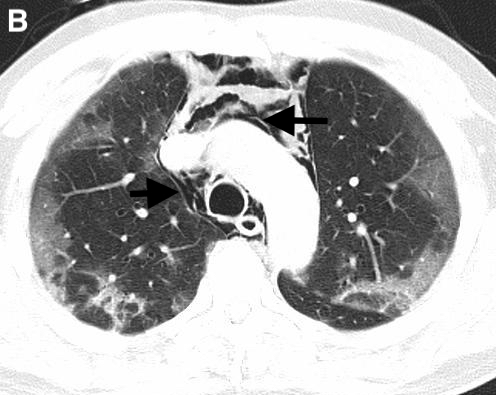

On hospital day five, the patient developed dysphonia, dysphagia, pleuritic pain, and subcutaneous emphysema in the supraclavicular region. His oxygen saturation was maintained at 97% with O2 at 3L / min through nasal cannula. A chest X-ray (Figure 1) and CT scan showed cervico-mediastinal emphysema (Figure 2) with pneumopericardium (Figure 3) and worsening lung infiltrates without pneumothorax.

Figure 3.